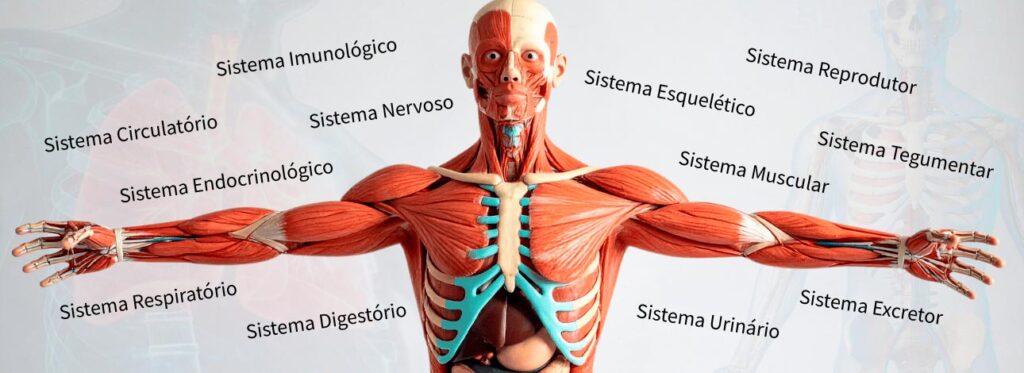

Descubra quais os sistemas do corpo humano e como cada um funciona para manter você vivo e em equilíbrio. Surpreenda-se com vídeos em 3D!